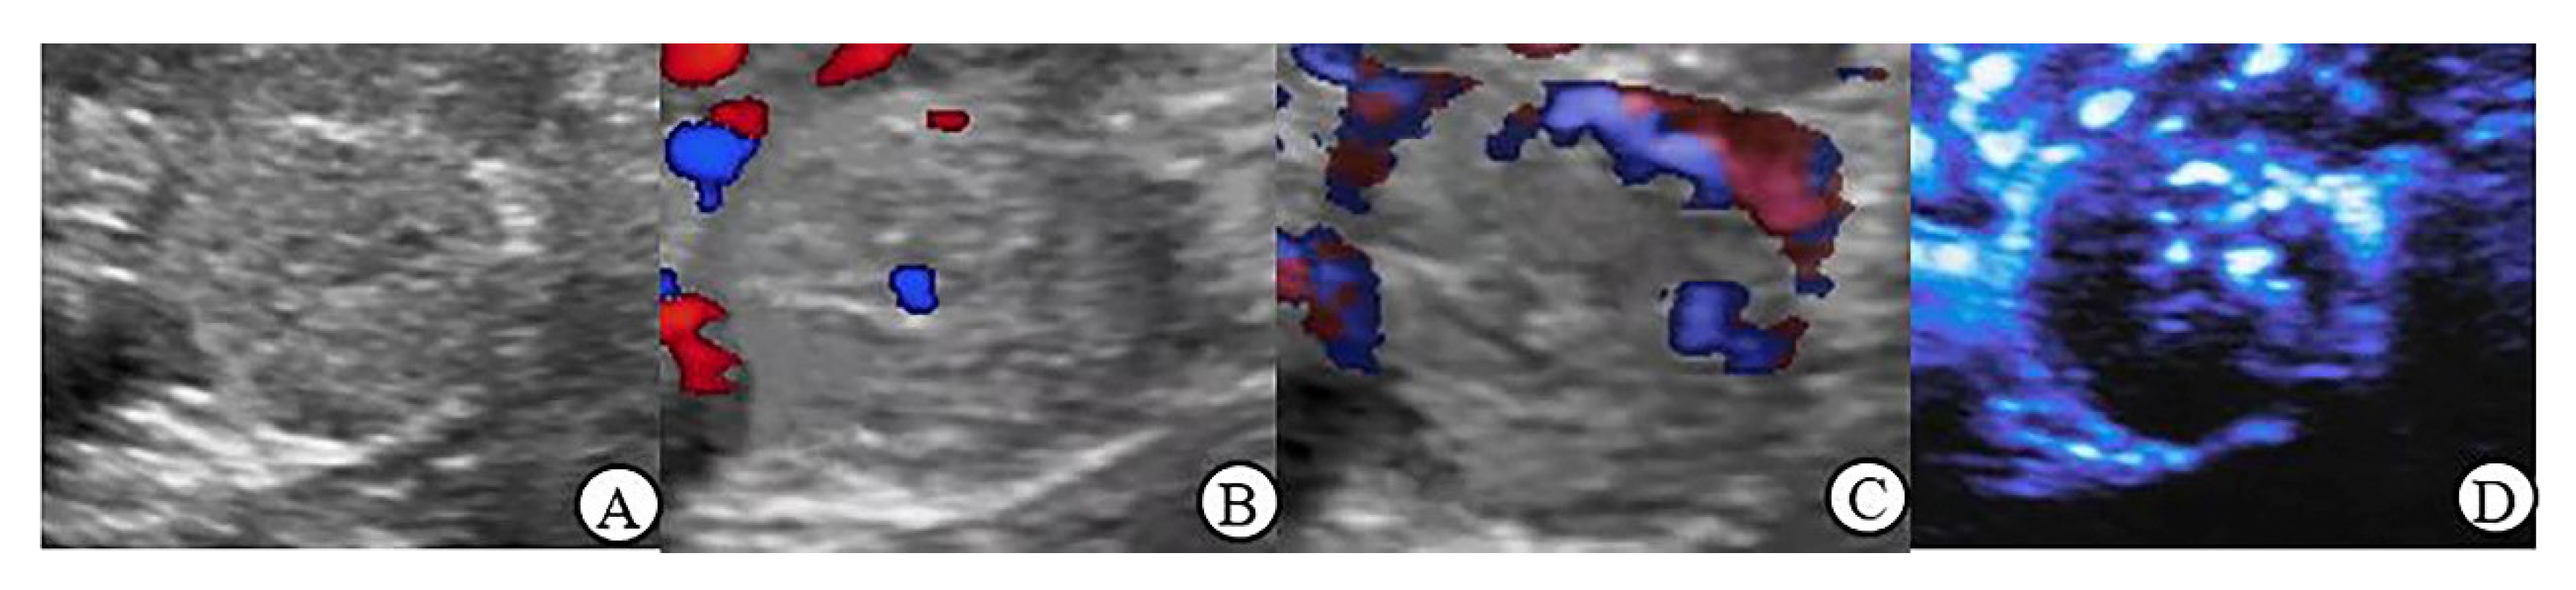

3.3. CDFI, PDI and MFI Evaluation of Blood Flow Characteristics in Benign and Malignant Renal Tumors ≤ 4 cm

3.5. Peripheral Blood Flow Characteristics of Renal Tumor in MFI Mode